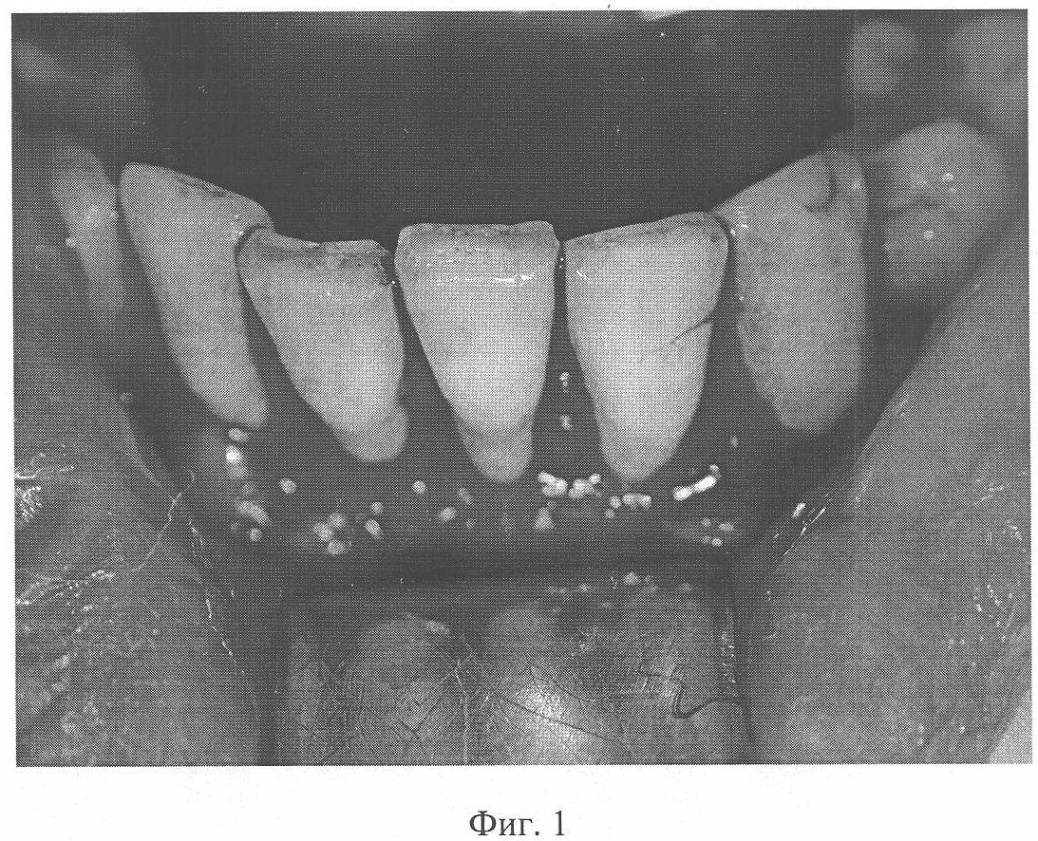

На фиг.1 изображено состояние альвеолярной части нижней челюсти больной Н. после удаления патологических тканей; на фиг.2 – состояние альвеолярной части нижней челюсти больной Н. после замещения костных изъянов мелкогранулированным пористым никелидом титана и установки тонкопрофильной тканевой системы поверх имплантационного материала.

Пример. Больная Н, 46 лет, обратилась с жалобами на подвижность зубов нижней челюсти. Из анамнеза: Считает себя больной в течение 15 лет, когда впервые стала отмечать кровоточивость десен и патологическую подвижность зубов, терапевтические мероприятия не дали положительного эффекта. Местно: Определялась патологическая подвижность 11, 12, 13, 14, 21, 22, 23 – II степени, их корни обнажены на длины. Слизистая оболочка альвеолярной части нижней челюсти отечна, гиперемирована, после зондирования кровоточит. Глубина пародонтальных карманов 6-8 мм. На ортопантомограмме (ОПТ) – неравномерная убыль костной ткани альвеолярной части нижней челюсти на 2/3 длины корней с четкими контурами. Обследование у терапевта выявило хронический гастрит и холецистит. Со стороны реологических показателей крови наблюдалось увеличение уровня растворимых фибринмономерных комплексов (РФМК) до 110 мкг/мл (норма – менее 35 мкг/мл), фактора Виллебранда (ФВ) до 180% (норма 60-120%), фибриногена до 6,0 г/л (норма 2-4 г/л), ПТИ до 114% (норма – 80-100%), укорочение активированного парциального тромбопластинового времени (АПТВ) до 35 сек (контроль 40 сек). Диагноз: Хронический генерализованный пародонтит нижней челюсти тяжелой степени, хронический гастрит, холецистит, хронический ДВС-синдром в стадии гиперкоагуляции, эндотелиоз. Лечение: Перед оперативным вмешательством проведен сеанс АПФ с удалением 40%-ного объема циркулирующей плазмы и ее возмещением гемодинамическими и белковыми растворами, а также назначены препараты, улучшающие агрегационные свойства эритроцитов. Проведен курс терапии по поводу вышеуказанной патологии внутренних органов. Выполнены местные противовоспалительные мероприятия. Оперативное вмешательство на нижней челюсти согласно описанной технологии. Послеоперационный период протекал гладко, без осложнений, заживление ран первичное. Через 10 суток РФМК составили 65 мкг/мл, фибриноген – 3,4 г/л, АПТВ – 35 сек (контроль 38 сек), ПТИ – 94%, тромбоциты – 320 тыс/мкл, активные формы тромбоцитов – 36% (норма 1,5-17,7%). Данные реологические нарушения устранены проведением 2 сеансов ЦПФ. При осмотре спустя 12 месяцев от вмешательства патологической подвижности зубов не определялось, пародонтальные карманы отсутствовали, десна плотная, находилась ниже шеек зубов на 1 мм, имела бледнорозовый цвет. Отклонений со стороны гемостазиологических биохимических и иммунологических показателей крови не наблюдалось. Рентгенологически выявлено увеличение высоты альвеолярной части нижней челюсти ниже шеек зубов на 1 мм, очагов остеопороза, резорбции корней зубов и костной ткани не отмечено.